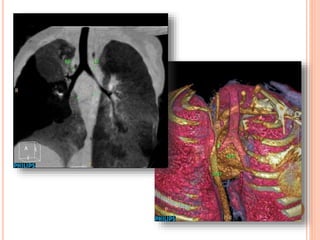

CASE #1 13MONTH-OLD BOY S/P TOF REPAIR

Huge RPA HugeMPA Severe PS Aneurysmal RVOT